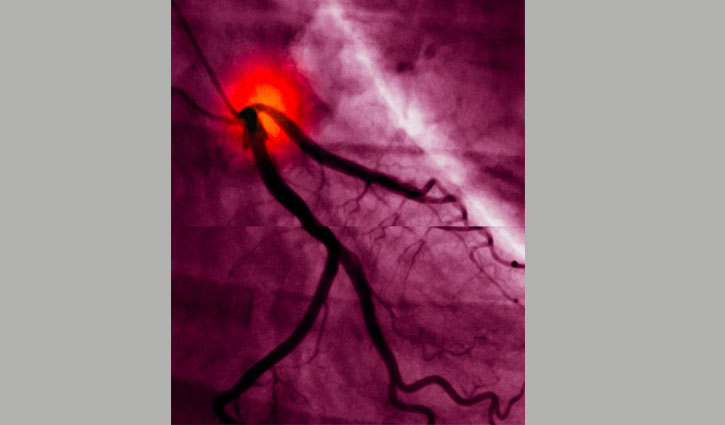

স্টেনোসিসে আক্রান্ত হার্টের ধমনীর স্ক্যানের ছবি। স্টেনোসিস এমন একটি প্রক্রিয়া যার ফলে ধমনী বা শিরা মারাত্মকভাবে চিকন হয়ে যায়। এর ফলে হঠাৎ হার্ট অ্যাটাক ও মারাত্মক কণ্ঠপ্রদাহ হতে পারে।